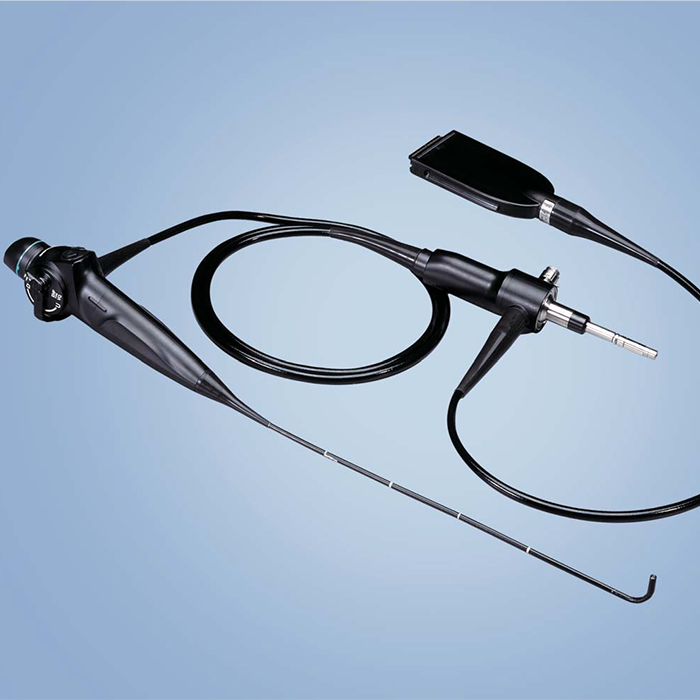

Olympus ENF-VH ENF-V3

Flexible Video Rhinolaryngoscope

HD clarity or a slim 2.6 mm distal end: two scopes cover most examination needs

Surprisingly Slim Diameter

The distal end of the ENF-V3 scope is only 2.6 mm in diameter, Also, the differencebetween diameters of the distal end and the insertion tube is minimal, This makesinsertion into tight nasal passages much easier. And with the CCD chip's improvement.even this slim scope delivers exceptional image quality.

OLYMPUS leads the world in endoscopes. We always listen carefully to physiciansand specialists on the medical front lines. Over and over, they have made twocomments that particularly resonated with us, “We want to make every diagnosismore accurate." and "We want smoother treatments for our patients." We drew uponour decades of endoscope expertise and combined it with OLYMPUS' proprietaryoptics technology. Now we can offer two new solutions: ENF-VH, with HD highdefinition, and ENF-V3, which maintains high image quality while reducing the distaend outer diameter to a mere 2.6 mm. With these two new products, OLYMPUS offersa new examination environment for rhino-laryngo videoscopes.

ENF-V3, crisp, high-resolution images with adistal end diameter of only 2.6 mm

- Distal end outer diameter 2.6 mm

- High image quality

- Exceptional illumination field

- Pre-freeze Function